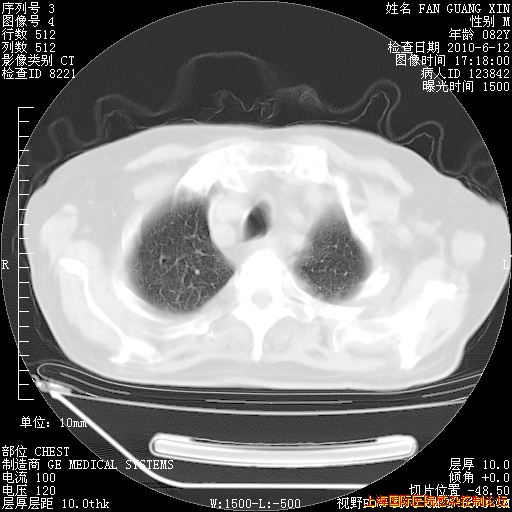

今天复查CT

今天CT

整整相隔30天的肺部CT好像有所好转啊。甲强龙减量第3天,需要观察体温。

海管,自昨日你和我通完话后,不知您岳父消化道症状有无缓解?体温怎样?阅读7.12日胸部ct,个人认为目前激素治疗是有效的,甲强龙减量是适宜的。因在抗痨治疗,需密切观察肝功、肾功能和血常规。不过,老年、长期住院和大量使用激素,很担心菌群失调发生